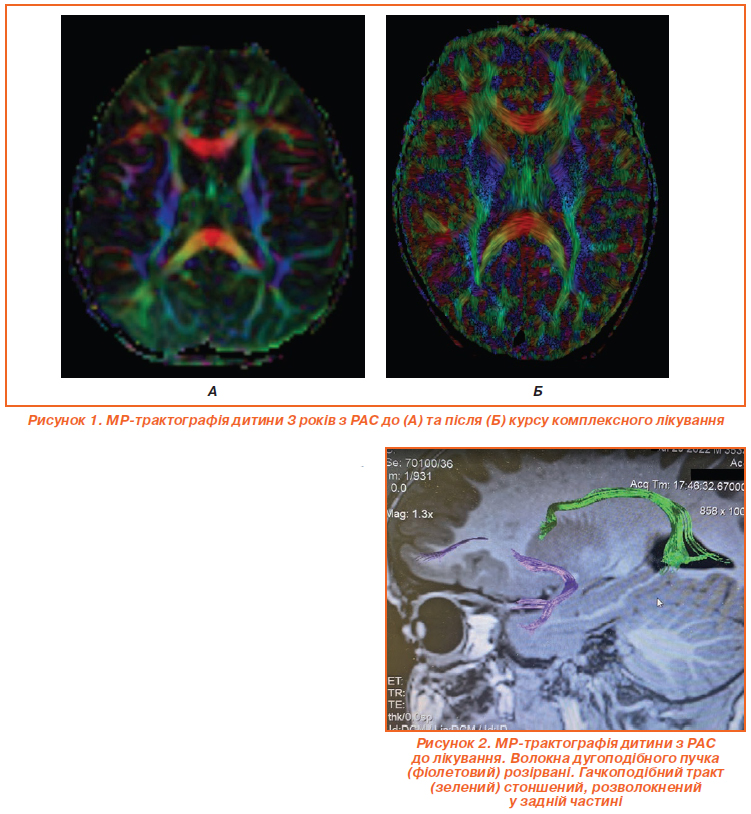

Для оцінки ефективності лікування застосовувалась МР-трактографія (рис. 1, 2). Рис. 1А відображає МР-трактографію мозку дитини 3 років з розладом аутистичного спектра (РАС) до лікування, видно характерні порушення в організації білої речовини. На аксіальному зрізі мозолисте тіло, представлене помаранчево-червоною дугоподібною структурою, виглядає стоншеним і асиметричним, з розривами трансверсальних волокон, що вказує на ослаблену міжпівкульну комунікацію, типову для РАС. Фронтальна ділянка з зеленими та жовтими асоціативними трактами, як-от superior longitudinal fasciculus, містить розірвані V-подібні структури з низькою щільністю, що корелює з труднощами в соціальній взаємодії та мовленні. У потиличних відділах візуалізуються фрагментовані inferior fronto-occipital fasciculus, а синьо-фіолетові кортикоспінальні тракти сформовані нерівномірно, що проявляється затримкою моторних навичок. Дугоподібні тракти (arcuate fasciculus) розірвані (рис. 2) та мають знижену фракційну анізотропію, що є маркером аномальної нейронної конективності при РАС.